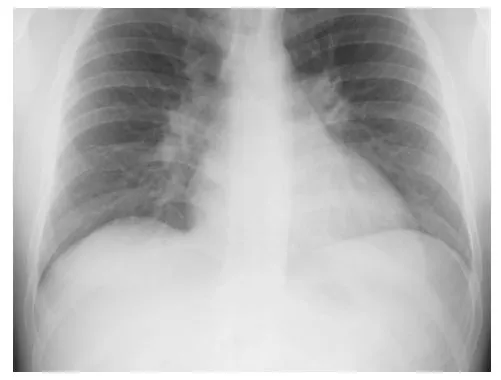

Evaluation included a chest x-ray (Fig. 1.1) that demonstrated increased pulmonary vascular markings, enlarged central pulmonary arteries, and cardiac enlargement involving the right heart chambers. An electrocardiogram revealed normal sinus rhythm with right axis deviation and right bundle branch block. The P-R interval was normal. Two-dimensional (2-D) echocardiogram was notable for moderate–severe right heart enlargement, mild tricuspid valve regurgitation, and a secundum atrial septal defect (ASD) measuring 22 mm. The estimated pulmonary artery systolic pressure was 40 mm Hg. The pulmonary valve was normal. A Holter monitor revealed no atrial or ventricular arrhythmias.

Fig. 1.1 Chest x-ray demonstrating enlarged cardiac silhouette, enlarged central pulmonary arteries, and increased pulmonary vascularity.

The chest x-ray findings of secundum ASD include cardiomegaly related to right-sided cardiac enlargement, central pulmonary artery enlargement, and prominent pulmonary vascularity secondary to pulmonary overcirculation.